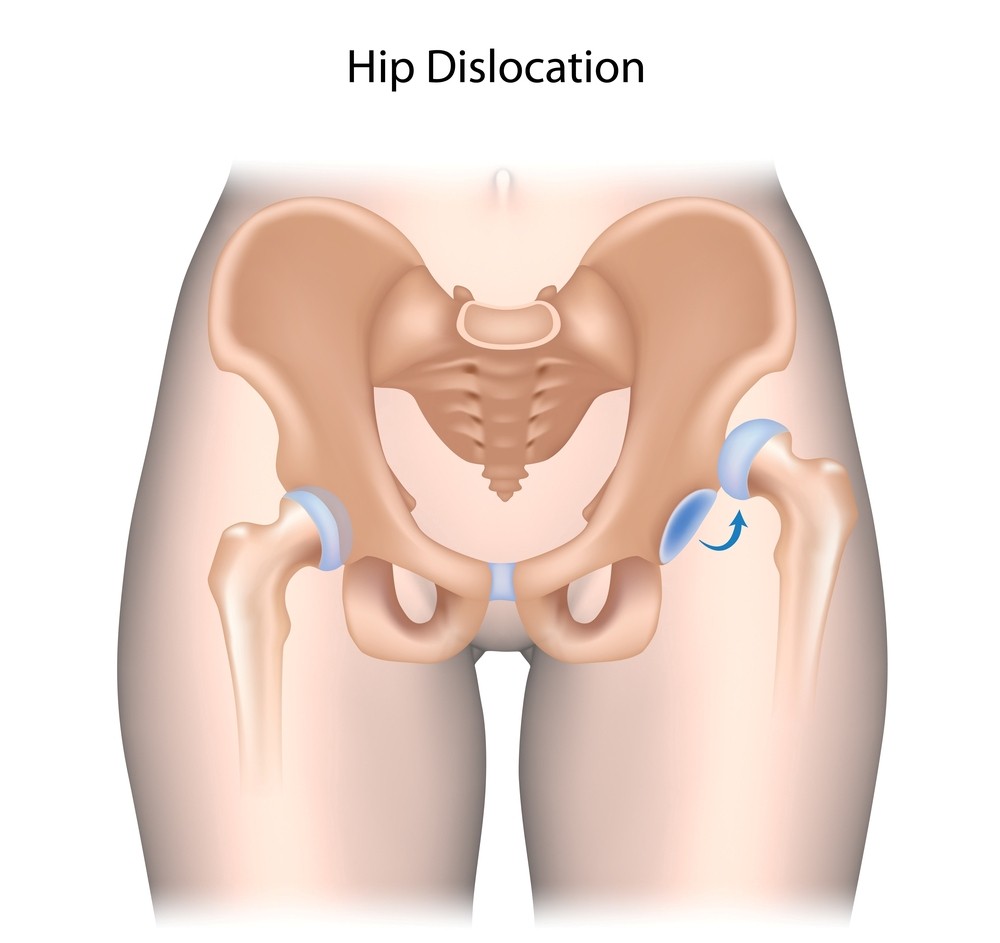

L’articolazione dell’anca, una delle più importanti e mobili del nostro corpo (è quella che ci permette di camminare), è costituita dal femore (l’osso della coscia) e dall’osso iliaco (che fa parte del bacino). L’estremità prossimale del femore (detta testa del femore), di forma convessa, trova alloggio in una cavità dell’osso iliaco, detta acetabolo.

Quando, a causa di un evento traumatico, la testa del femore fuoriesce dall’acetabolo, cioè dal suo alloggio naturale, si avrà una lussazione dell’anca, evento estremamente doloroso e invalidante.

La lussazione dell’anca può essere incompleta, quando il contatto fra le ossa che costituiscono l’articolazione viene in parte conservato, o completa, quando il contatto fra le ossa viene a mancare completamente.

Nella stragrande maggioranza dei casi, questo tipo di infortuni causa una lussazione posteriore: in pratica la testa del femore fuoriesce dall’acetabolo portandosi indietro e leggermente in alto rispetto a quest’ultimo. Purtroppo, non di rado questo infortunio è accompagnato dalla frattura dell’acetabolo e/o della testa del femore.